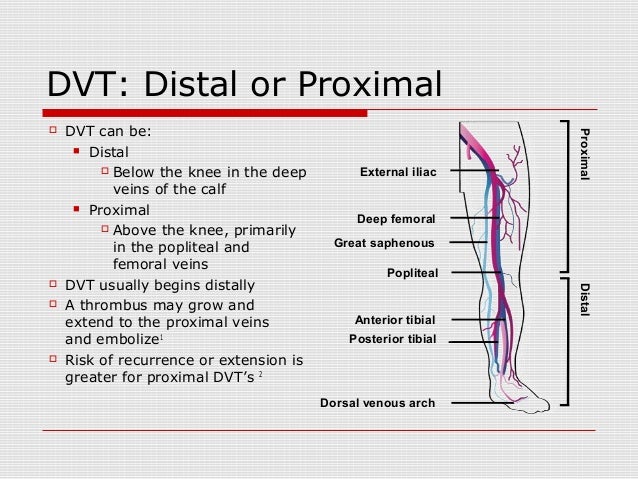

Vte 2014

www.slideshare.net

www.slideshare.net

vte distal proximal dvt veins calf

Prognostic Value Of Distal (vs. Proximal) Isolated Deep Vein Thrombosis

www.researchgate.net

www.researchgate.net

Key Differences In Presentation, Outcomes For Distal Versus Proximal

medicalxpress.com

medicalxpress.com